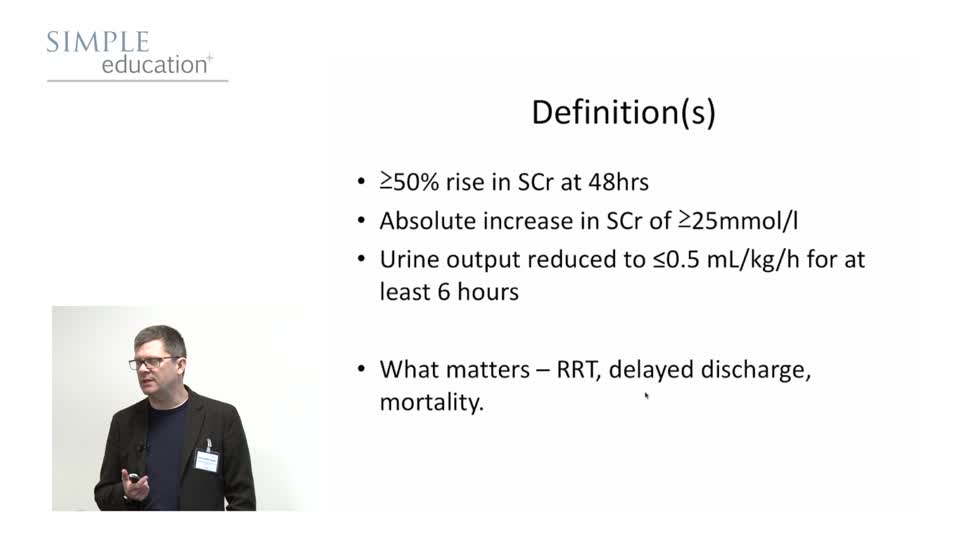

Prevention of Contrast Induced Nephropathy: Fact, Fiction and Fantasy - Christopher Baker

Simple Education